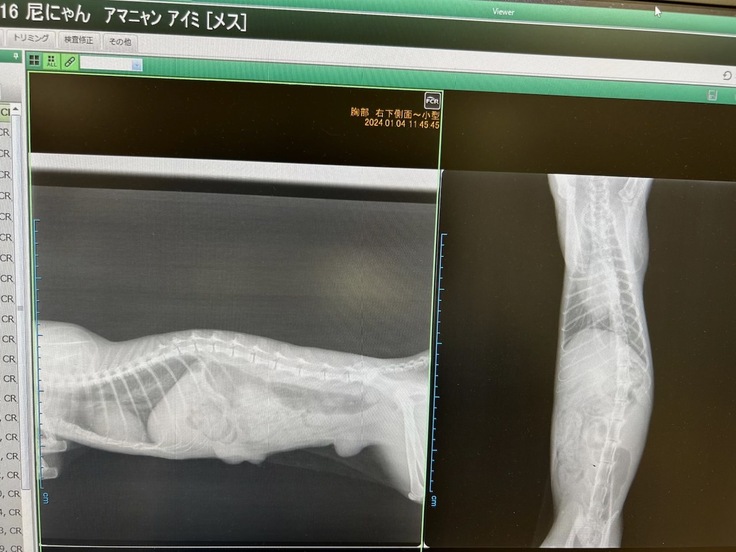

愛美ちゃんの乳腺腫瘍が見つかりました。

乳腺腫瘍は避妊手術をしていたら防げる病気です。

昨年の年末に愛美ちゃんの胸にしこりを見つけ

動物病院にすぐに行きました

検査結果は「乳腺腫瘍」この段階では

肺には転位が見られなかったので

年明けに手術をすることにしました

手術前の検診で愛美ちゃんの身体には

植物の種をまいたように

小さな腫瘍があるのが分かりました

完全に取り切れないかもしれない・・・

大変難しい手術になると言われました